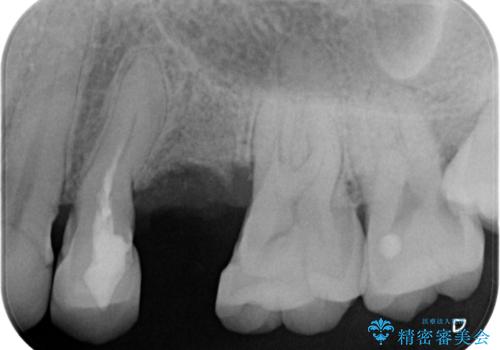

X線、歯周組織検査の結果、残すことができない歯周病の進行が左上小臼歯に認められました。

抜歯後は、インプラントではなくブリッジを選択されました。

最終的なブリッジの清掃性を高めるため、歯ぐきのボリュームがこれ以上減少しないよう抜歯時に歯槽堤保存術を行うような工夫をしています。

治療前よりも高い位置で歯ぐきが保たれ、清掃性の高いブリッジ治療を行うことができました。